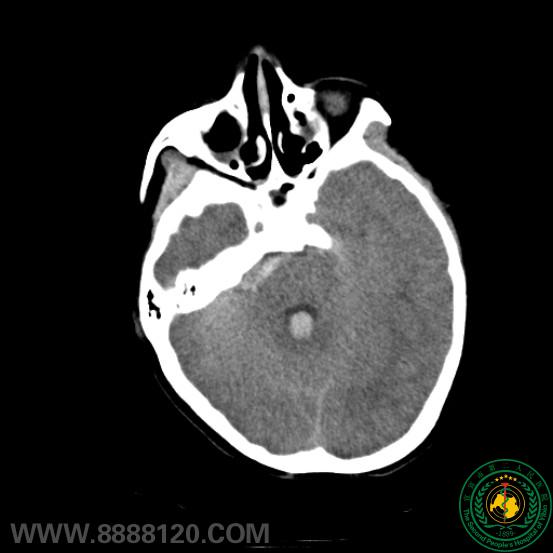

我科完成一例小脑前下动脉 (AICA )动脉瘤介入治疗

我科完成一例小脑前下动脉 (AICA )动脉瘤介入治疗9584

宜宾市第二人民医院 图文